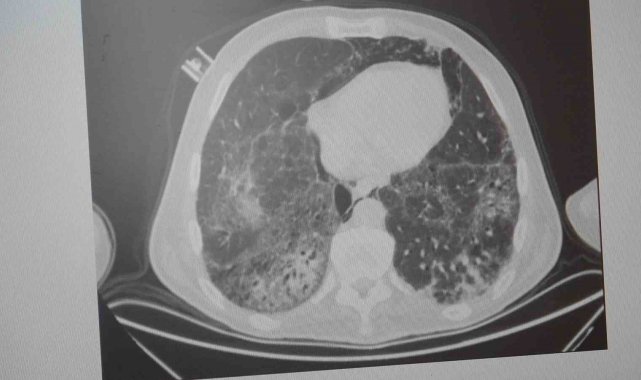

KOAH'ın akciğer dokusunu tahrip eden bir hastalık olduğunu ve bu nedenle de hastaların enfeksiyona açık hale geldiğine dikkat çeken Karakurt, "Akciğer dokusunun tahrip olduğu her durumda hastaların enfeksiyona karşı eğilimi artar ve enfeksiyona yakalandıkları zaman bunun geçmesi güç olur. KOAH'lı hastalar zatürre geçirdikleri zaman öksürük ve balgam artışı gibi bir takım belirtiler gelişir. Ayrıca ateşin 38,5 derecenin üstüne çıkması, nefes darlığının artması, titremeyle birlikte ateşin yükselmesi ve bir takım bilinç bozukluğu gibi belirtiler hastanın zatürre olduğunu gösterebilir. Bu nedenle hastaların erkenden doktora başvurmaları önemlidir" şeklinde konuştu.

Hastalarda bronşit ve zatürrenin ayırt edebilmesi için belirtilerin doğru tespit edilmesi gerektiğini vurgulayan Karakurt, "Hem zatürrede hem de bronşitte hastalarda öksürük, balgam ve ateş görülür ama burada ikisini ayırt etmek lazım. Bronşit daha çok hava yollarının yani bronşların iltihaplanmasıdır. Zatürre ise hava yollarının uçlarında bulunan ve karbondioksit değişimini sağlayan alveollerin yani hava keselerinin iltihaplanmasıdır. Bronşitten ölüm pek görülmez ama zatürre tehlikelidir; aşağı yukarı yüzde 10 gibi bir ölüm oranıyla seyreder ve bu ölüm oranı yaş arttıkça artar. Ayrım için ateşin yüksek olup olmamasına ve hastada bilinç bozukluğu, solunum sayısının artması ve morarma gibi belirtiler görüldüğü takdirde zatürre olabileceğini düşündürür. Bu gibi durumlarda en kısa zamanda bir sağlık kuruluşuna başvurmak gereklidir" ifadelerini kullandı.